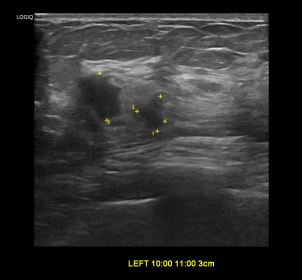

상기환자 혈성분비물 및 만져지는 멍울로 정밀검사위해 내원하신 40대 여성분으로

좌측유방 혹 총조직검사 시행해 유방암 진단되었습니다.